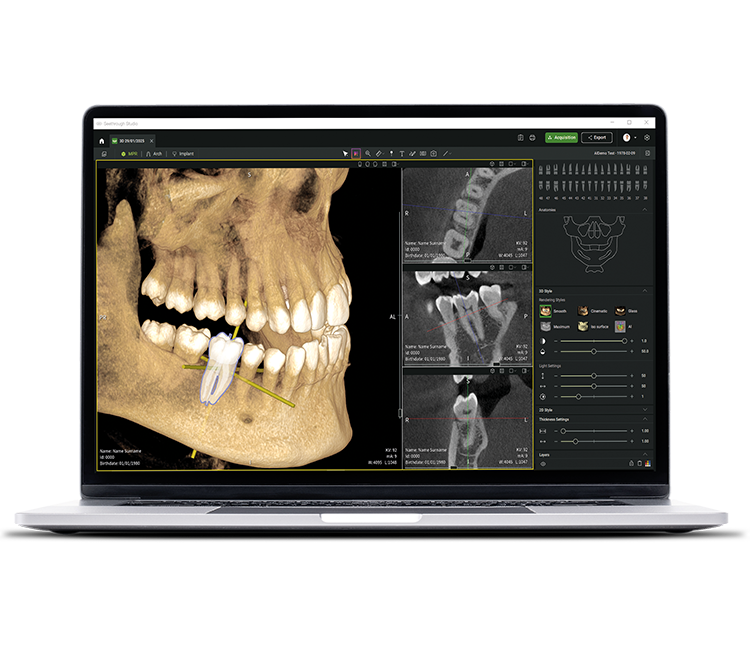

See tomorrow. See a new level.

Neben ausgereiften Hardware-Technologien ist die revolutionäre Seethrough Studio Software der entscheidende Faktor für den hohen Standard des gesamten W&H-Imaging Portfolios: Mit nützlichen Funktionen und fortschrittlichen Algorithmen ist Seethrough Studio eine Komplettlösung, die die Bildgebung und digitale Workflows in der Zahnmedizin auf ein neues Niveau hebt.

Integriertes Implantatplanungstool

Über die herausragende Bildqualitätund die intuitive Bedienung hinaus bietet Seethrough Studio zahlreiche nützliche Funktionen wie etwa das standardmäßig integrierte Implantatplanungstool für eine einfache Visualisierung und Vorbereitung der Behandlung.

KI-unterstützte Funktionen

Seethrough Studio verwendet Verfahren der künstlichen Intelligenz zur Unterstützung der Visualisierung und Verwaltung klinischer Bilddaten. Die Software stellt automatisierte Funktionen bereit, einschließlich der Segmentierung relevanter anatomischer Strukturen in 3D-Volumenmodellen, der Ausrichtung einzelner Zahnachsen, der Generierung der Zahnbogenkurve sowie der Nachverfolgung (Tracing) des Nervus alveolaris inferior.